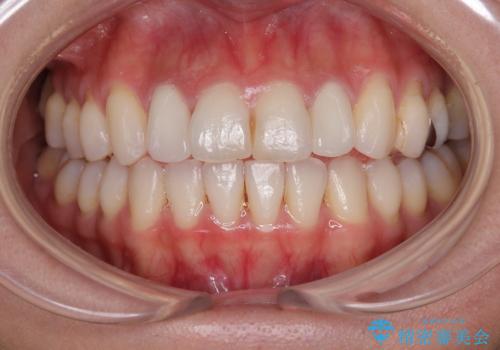

自然できれなオールセラミッククラウンになり、とても満足されました。